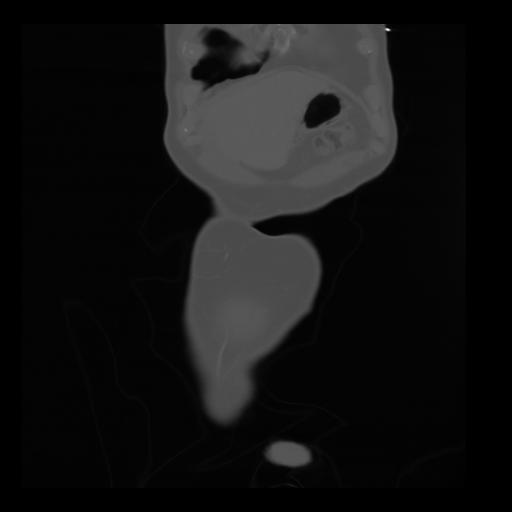

35 CUERPO,CE,Coronal,3.000,CUERPO,Coronal,